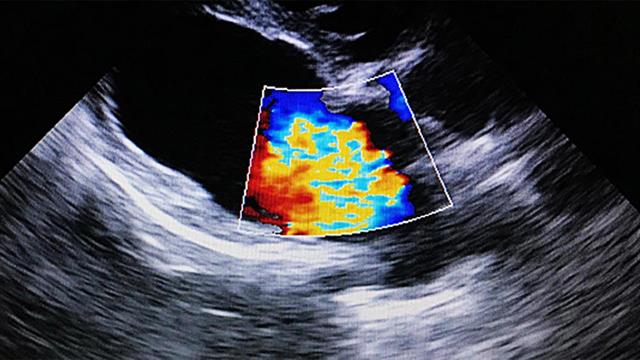

Η περίπτωση της μυοκαρδίτιδας σε νοσήσαντες από Covid-19 ασθενείς εμφανίστηκε και σαν ξεχωριστή εκδήλωση της νόσησης ανεξάρτητα από την περίπτωση πολυοργανικής ανεπάρκειας που περιγράφηκε προηγούμενα. Η διάγνωση αυτής της απειλητικής για τη ζωή επιπλοκής Covid-19 στηρίζεται σε μια σειρά κλινικοεργαστηριακών παραμέτρων με σαφή διαγνωστική ακρίβεια.

Όντας ως μεμωνομένη επιπλοκή νόσησης από Covid-19, η πλειονότητα των περιπτώσεων αντιμετωπίζεται αποτελεσματικά. Εντούτοις οι μακροχρόνιες επιπτώσεις μιας τέτοιας επιπλοκής, δηλαδή της εμφάνισης μυοκαρδίτιδας από την νόσηση Covid-19 απαιτούν περιοδική παρακολούθηση για το ενδεχόμενο ανάπτυξης μιας μορφής καρδιακής ανεπάρκειας που χαρακτηρίζεται διατατική μυοκαρδιοπάθεια.

Εδώ θα πρέπει να αναφερθεί οτι σήμερα είμαστε στη θέση να εντοπίσουμε εκείνους τους λίγους ασθενείς με τέτοιες αρρυθμίες που διατρέχουν κίνδυνο όταν εφαρμοστεί μια εμπεριστατωμένη αξιολόγηση αυτών, λαμβάνοντας υπόψη αναίμακτες εξετάσεις και δεδομένα από το ιστορικό, το ηλεκτροκαρδιογράφημα, το υπέρηχοκαρδιογράφημα, ή ακόμη και τη μαγνητική τομογραφία καρδιάς, σε ελάχιστες δε περιπτώσεις καταφεύγοντας σε επεμβατικές εξεταστικές μεθόδους στο ηλεκτροφυσιολογικό εργαστήριο.